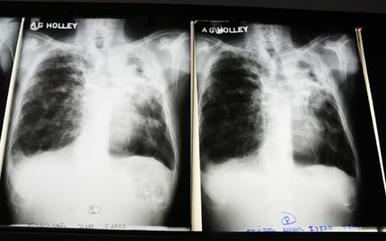

The World Health Organization recently reported that the number of cases of tuberculosis has been falling since 2006. Also, fewer people are dying from TB. But a study by researchers at the University of California, San Francisco, says smoking could threaten this progress.

Nearly 20 percent of all people use tobacco, and millions of non-smokers get sick from breathing the smoke. The new study predicts that smoking will produce an additional 34 million TB deaths by 2050.

Smoking does not cause tuberculosis; bacteria cause the infection. But the study says smoking affects the nervous system in a way that makes an inactive case of TB more likely to develop into an active one.